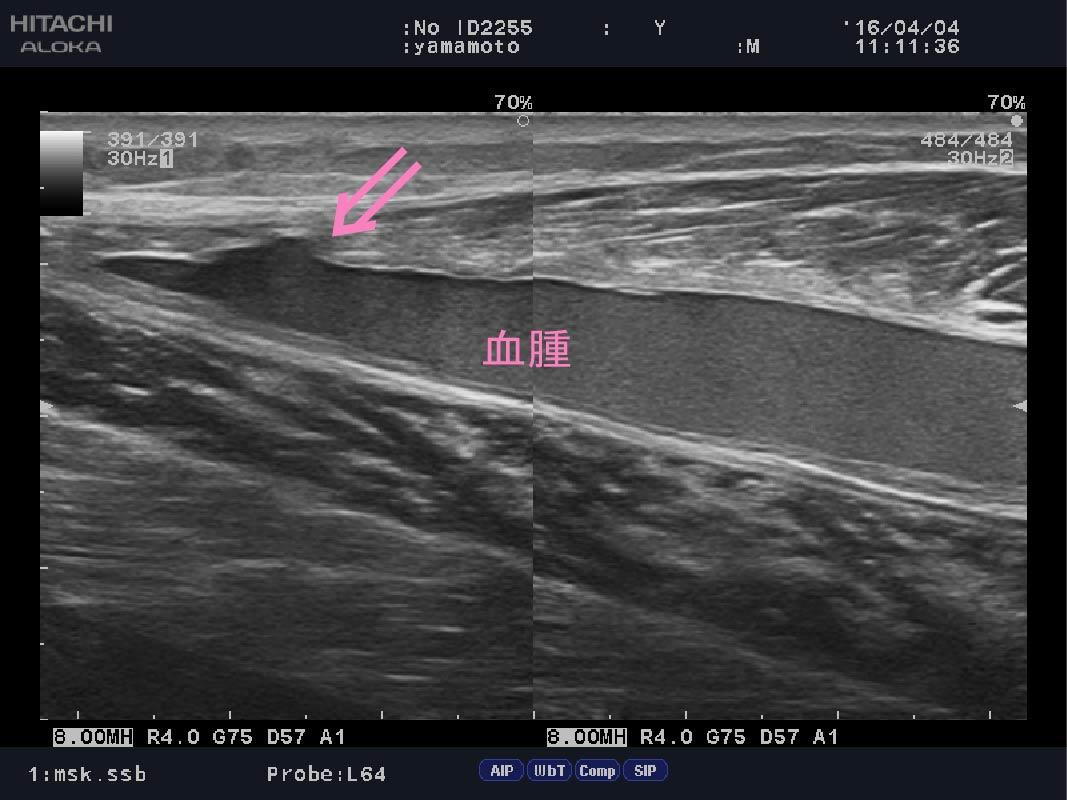

ふくらはぎの肉離れ

西武新宿線 東伏見駅南口『まる接骨院』です。 ここ数日、気温の低下からか、「肉離...